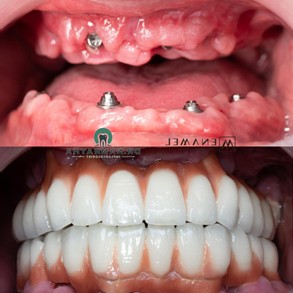

The fixed teeth provided immediate stability and function, allowing Jason to regain normal activities like eating, speaking, and smiling without discomfort.

The results of the full mouth rehabilitation were nothing short of exceptional. Jason was thrilled with the outcome — not only did he regain full functionality, but his new smile looked completely natural. The All-on-6 implants and zygomatic implants successfully restored his confidence, and his quality of life improved dramatically.

Jason’s restored smile and renewed ability to chew and speak comfortably made a significant difference in his day-to-day life.